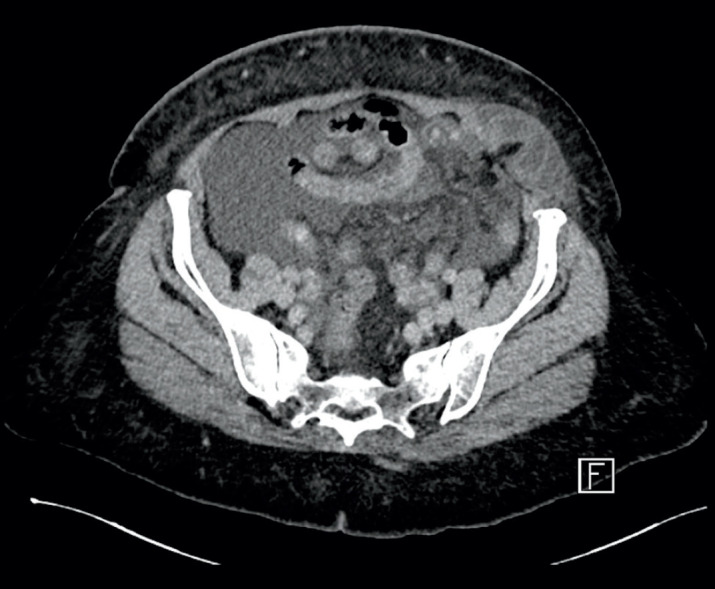

Case presentation: A 65-year-old lady, presented to our emergency department complaining of a left lower quadrant (LLQ) abdominal pain associated with a painful swelling for 9 hours duration. Upon assessment, the patient was jaundiced and haemodynamically stable. Abdominal examination revealed a soft and lax but distended abdomen, with irreducible tender swelling over the LLQ, measuring around 3x2 cm. Laboratory investigations showed anemia, hypoalbuminemia, hyperbilirubinemia, lactic acidosis and prolonged coagulation profile. A contrast-enhanced computed tomography (CT) scan of the abdomen showed evidence of incarcerated left spigelian hernia. Moreover, advanced cirrhosis of the liver was detected with hypertrophy of the caudate lobe, extensive ascites and splenomegaly. After establishing the diagnosis of incarcerated spigelian hernia, with a picture of advanced liver cirrhosis, Child-Pugh-Turcotte (CPT) score of C and a Model for End-Stage Liver Disease (MELD) score of 19 and Mayo score for post-operative mortality of 16% in 7 days and 53% in 30 days. Given the patient's condition which necessitates urgent operative intervention beside the risk of decompensation of pre-existing liver disease and high mortality. Decision was made to proceed with laparoscopic hernia repair. Intraoperatively, ischemic small bowel segment was resected with creation of end ileostomy. Conventional anatomical repair of the hernia defect was performed. Postoperatively, the patient was managed and resuscitated in critical care unit and then discharged home in a satisfactory condition on post-operative day 15. She passed away prior to liver transplantation, thirty-two days post-operatively in a different institution.